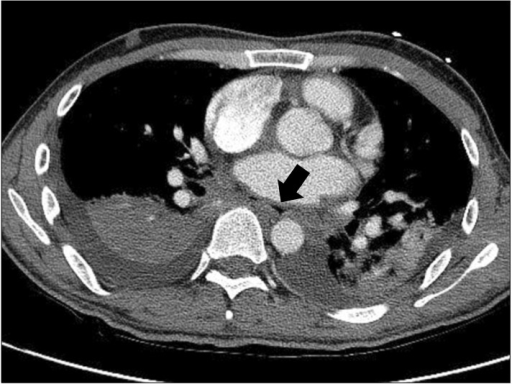

Successful management of atrio-esophageal fistula after cardiac radiofrequency catheter ablation. Shim HB, Kim C, Kim HK, Sung K - The Korean journal of thoracic and cardiovascular surgery (2013)